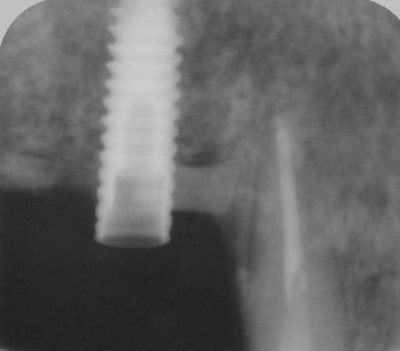

pour illustrer cette utilisation du bioactys, voici un cas (ce matin, mise en focntion des implants à 7 mois post_op)

C'était un peu limite non pour la pose immédiate, faible hauteur osseuse initiale.

pour la pose immédiate, çà dépend aussi du type d'implant utilisé...ici c'est des superline dentium...;-)

ils ont vraiment une super stab primaire, et leur design est parfait pour les zones sous sinusienne...entre autre....parce que pour l'instant, mis à part le manque d'un repère visible sur le préhenseur de la position de l'hex antirotationnel, j'ai pas encore trouvé de défaut au système...

ici c'est un mix (pour un impératif perso): en 25 un easy-implant master s puis 2 dentium superline.

Le easy c'est du sablé au corindon et les dentium sablés-mordancés SLA http://www.dentogem.com/viewpage.php?pageid=48

j'ai donc procédé à la mise en fonction ce matin, 7 mois après l'intervention. Mise en place de piliers de cicatrisation assez hautes et surtout de diamètres en adéquation avec une PM et 2M. je prends l'empreinte dans 3 semaines , la gencive sera belle autour des piliers.